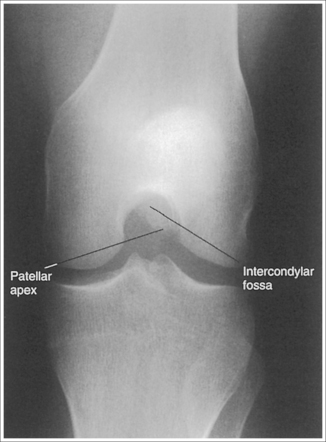

The knee demonstrates an AP projection. The medial and lateral femoral epicondyles are in profile, the femoral condyles are symmetrical, the intercondylar eminence is centered within the intercondylar fossa, and the tibia is superimposed over 0.25 inch (0.6 cm) of the fibular head.

• To obtain an AP knee projection, place the patient in a supine position with the knee fully extended. Internally rotate the leg until an imaginary line drawn between the medial and lateral femoral epicondyles is positioned parallel with the IR (Figure 6-71). This positioning places the medial and lateral femoral epicondyles at equal distances from the IR as well as medially and laterally in profile, respectively. It also centers the intercondylar eminence within the intercondylar fossa and draws the fibular neck and a portion of the fibular head from beneath the tibia.

The patella lies just superior to the patellar surface of the femur and is situated slightly lateral to the knee midline. The intercondylar fossa is partially demonstrated.

• Center the central ray to the midline of the knee at a level 1 inch (2.5 cm) distal to the palpable medial epicondyle to place the knee joint in the center of the exposure field. (As long as the knee remains extended, an alternative central ray placement is 0.5 inch (1.25 cm) distal to the patellar apex.) Open the longitudinal collimation enough to include one fourth of the distal femur and proximal lower leg. Transverse collimation should be to within 0.5 inch (1.25 cm) of the knee skin line.